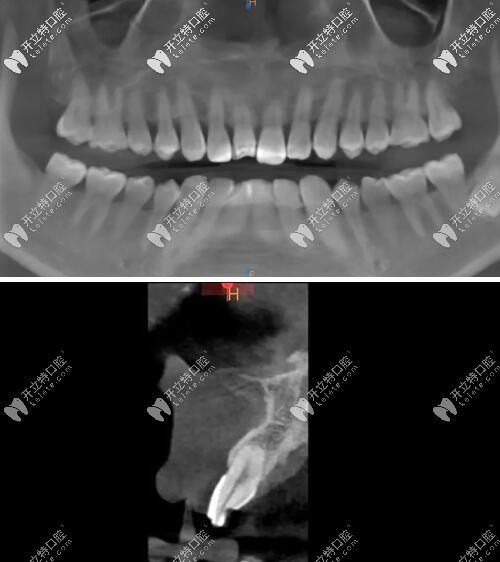

影像學檢查

門牙磕斷傷及牙根影像學檢查

被磕的牙冠根向折裂,直達骨下;

牙根骨量充足;

牙長軸和牙槽骨的方向基本一致。

術(shù)后CBCT顯示植入正確的三維位置,種植體唇側(cè)骨量充足;

瑞士iti鈦親水BL 4.1mm*10mm種植體